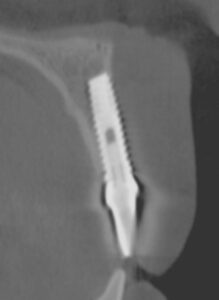

This article focuses on an alarming issue of implants loosing support and integration due to excessive soft tissue pull or tension from a shallow vestibule and/or dense frenum pull. We now have an abundant number of cases that exhibit tissue recession and possibly late loss failure. For example, Figures 1A-1C show a case of late implant failure. In 1996, the patient received

an implant on tooth No. 8. The immediate result was very good, both functionally and aesthetically (Figure 1A). However, the 2007 follow-up visit revealed severe gingival recession (Figure 1B depicts the recession and distinct frenum pulls). The cross-sectional image from 2007 (Figure 1C) demonstrates the lack of bone in the facial and apical aspects of the implant. The presence of frenum pulls (evident in Figure 1A from 1996) should have been a reason for concern. We believe that a prophylactic release of the frenum pull prior to implant loading would have prevented such outcome. Today, we would have addressed the frenum pull with a CO2 frenectomy prior to implant loading.